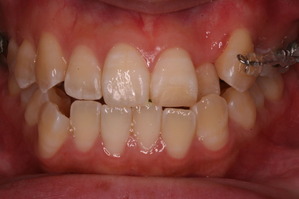

今回の症例はAの治療期間を短縮する場合です。

上方向からみると奥歯が頬方向に傾いております。

つまり例としては1と3に当てはまります。

私の場合、治療開始時から全部つけるのをあまり好みません。必要な部分のみ装置をセットすることが多いいです。

上の奥歯の部分を注目してください。親知らずの前の歯が2本抜歯してるのがわかると思います。

つまり、この時点で上顎だけで3本も抜歯してます。そういう意味では患者さんは不安になりますかね(笑)